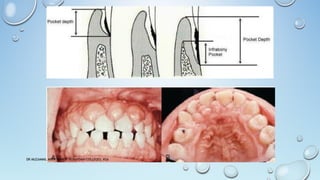

INDICATIONS OF GINGIVECTOMY

Elimination of suprabony pockets, regardless of their depth, if the pocket wall is fibrous

and firm.

Elimination of gingival enlargements.

Elimination of suprabony periodontal abscesses.

CONTRAINDICATIONS OF GINGIVECTOMY

The need for bone surgery or examination of the bone shape and morphology.

Situations in which the bottom of the pocket is apical to the mucogingival junction.

Esthetic considerations, particularly in the anterior maxilla.